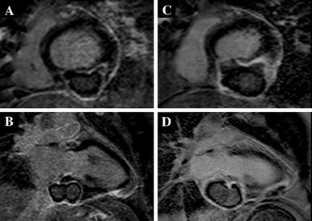

Fig. 1